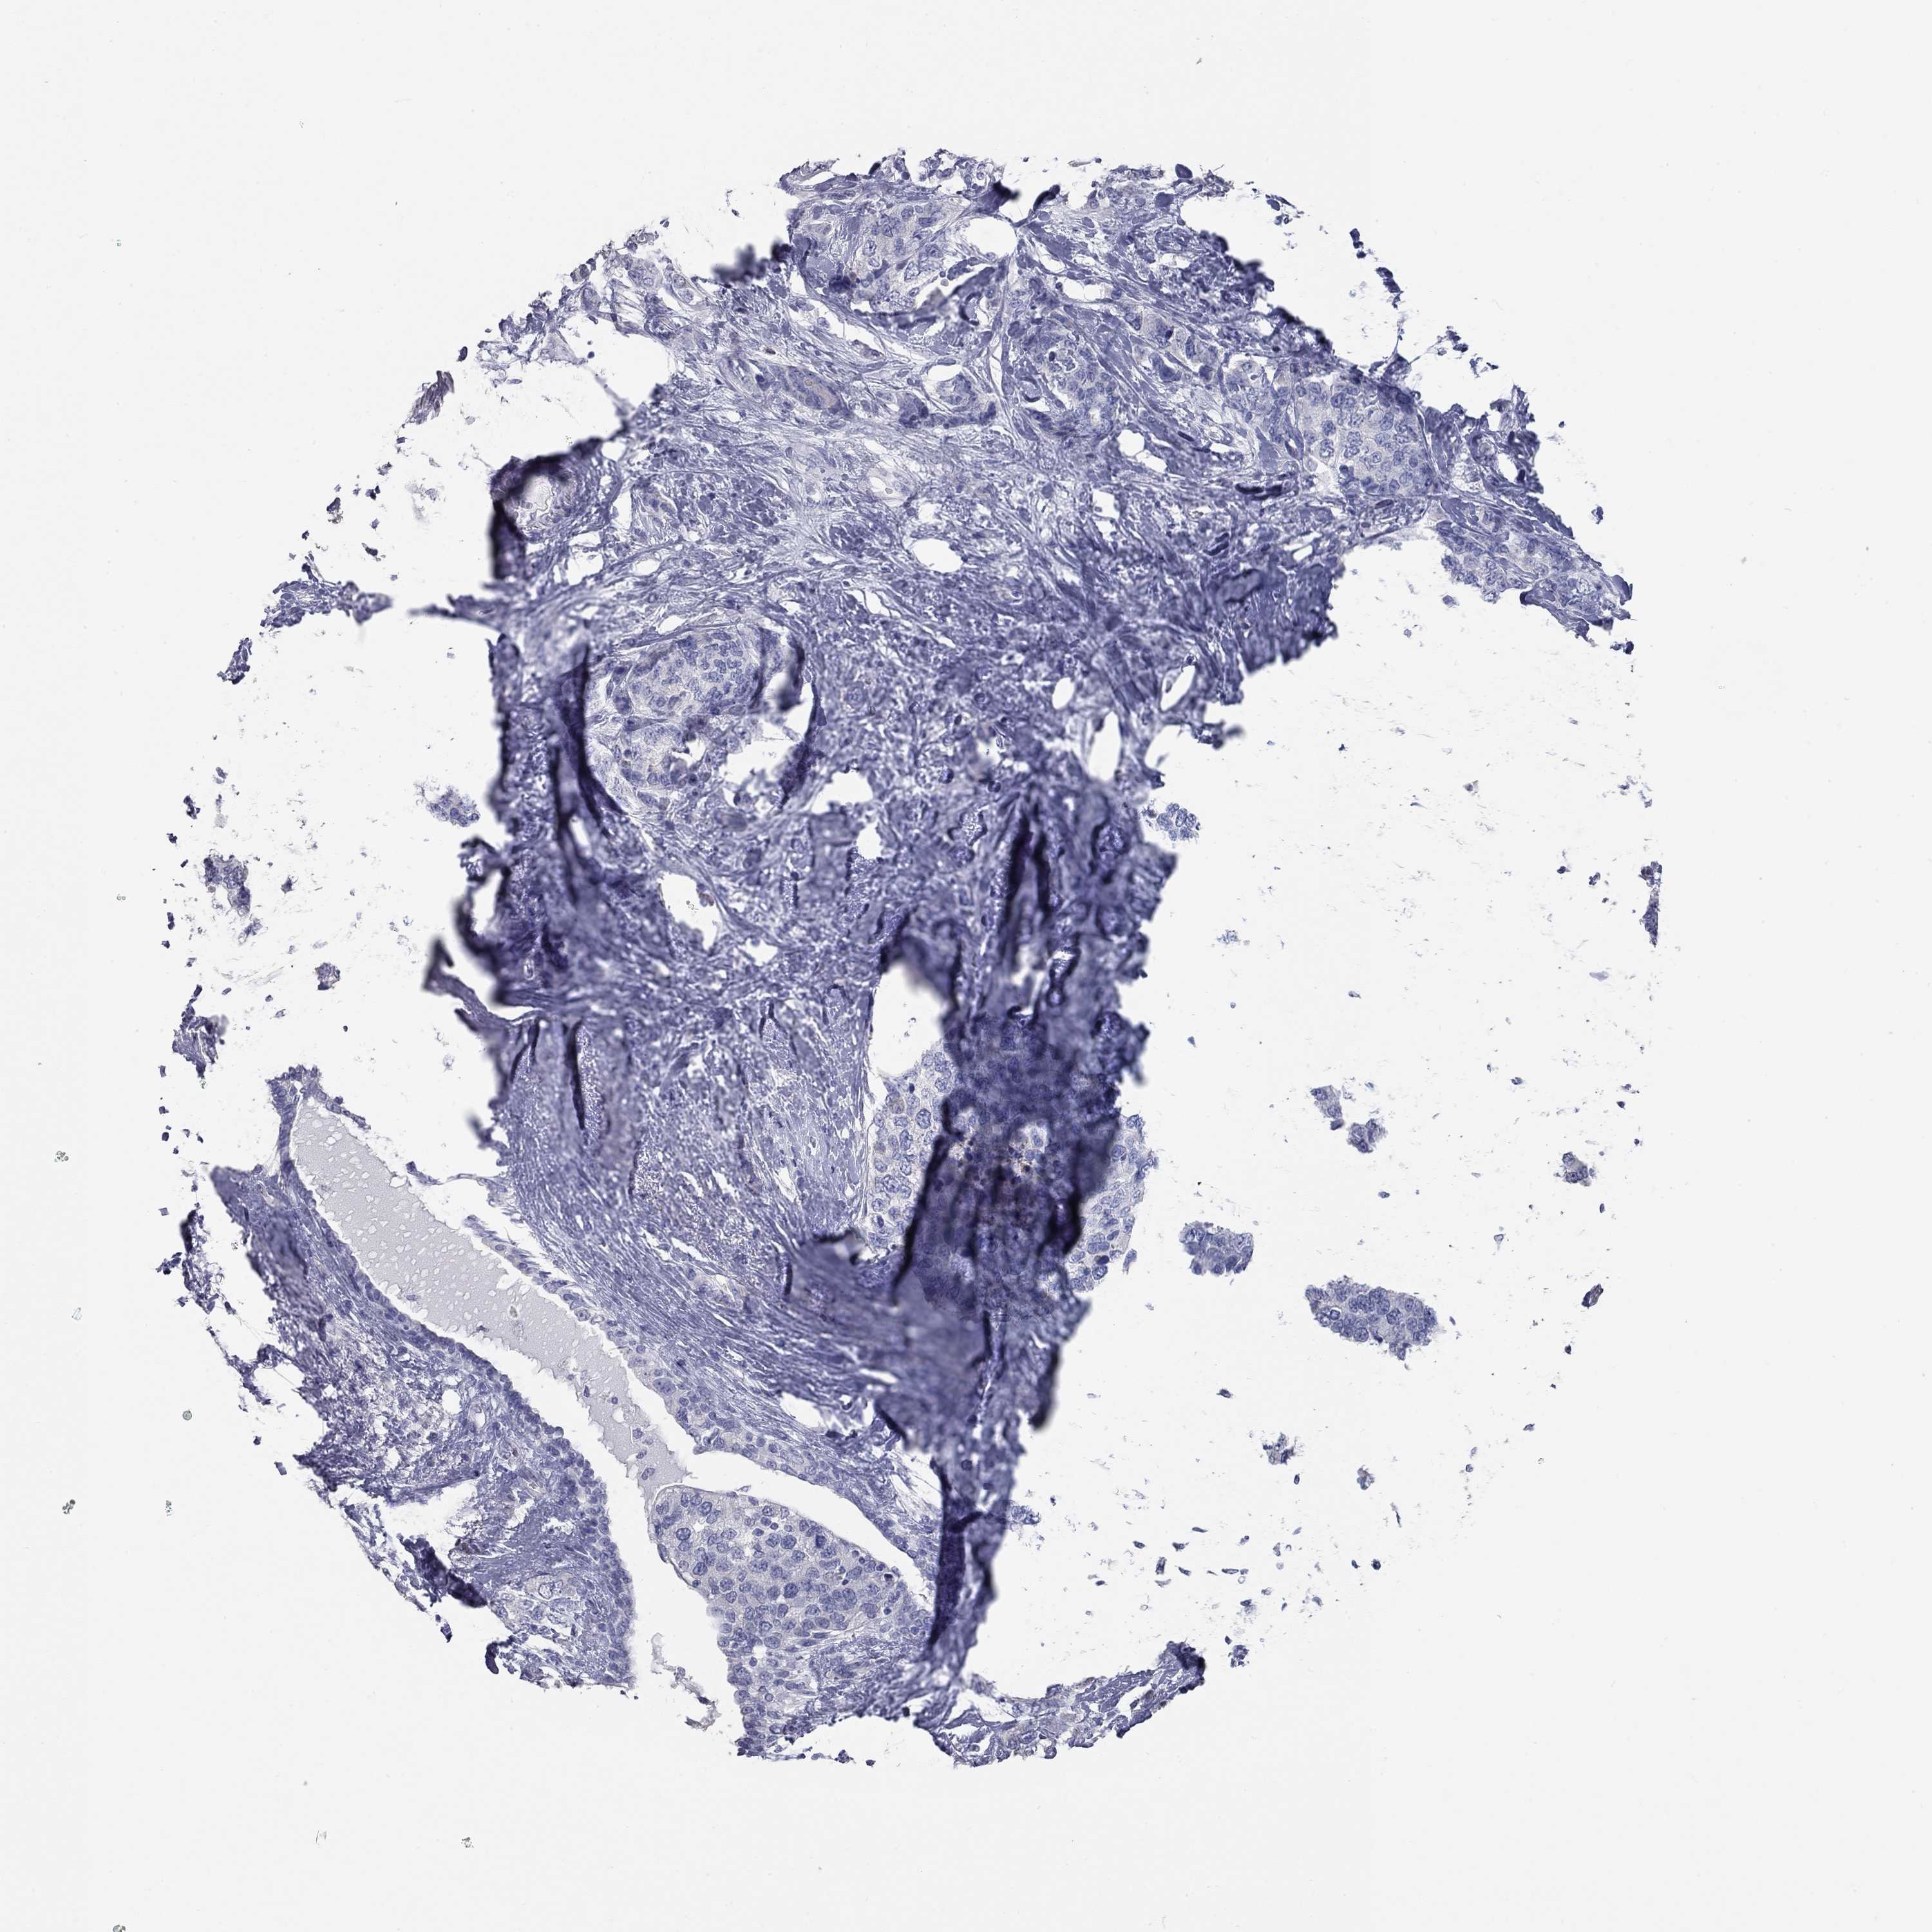

CANCER BREAST CANCER Show tissue menu

BRCA TCGA BRCA VALIDATION PROTEIN EXPRESSION

ANTIBODIES

AND

VALIDATION